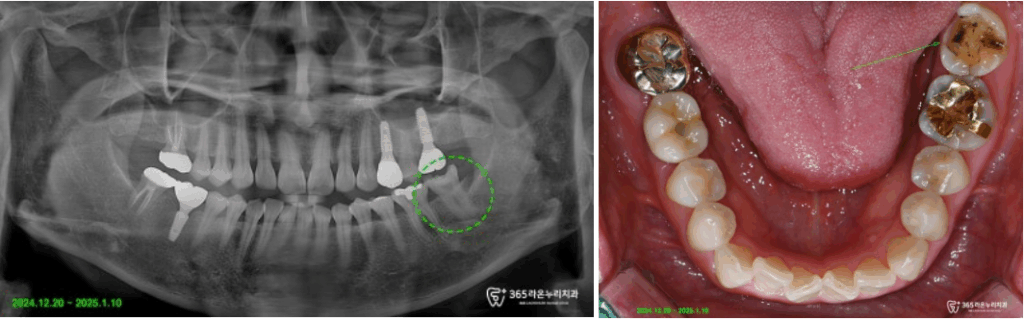

파노라마 촬영 및 진단 포토를 통해

구강 검진을 진행한 결과

보철 내부의 2차 우식으로 범위가

커져서, 인레이로는 부족하고 더 적절한

수복이 필요할 듯하여 크라운 치료에 대해

설명드렸습니다.

우선 왼쪽 아래턱 어금니의 기존 보철

하방의 우식(충치)치질 제거를

진행해드리고 있는 모습입니다.